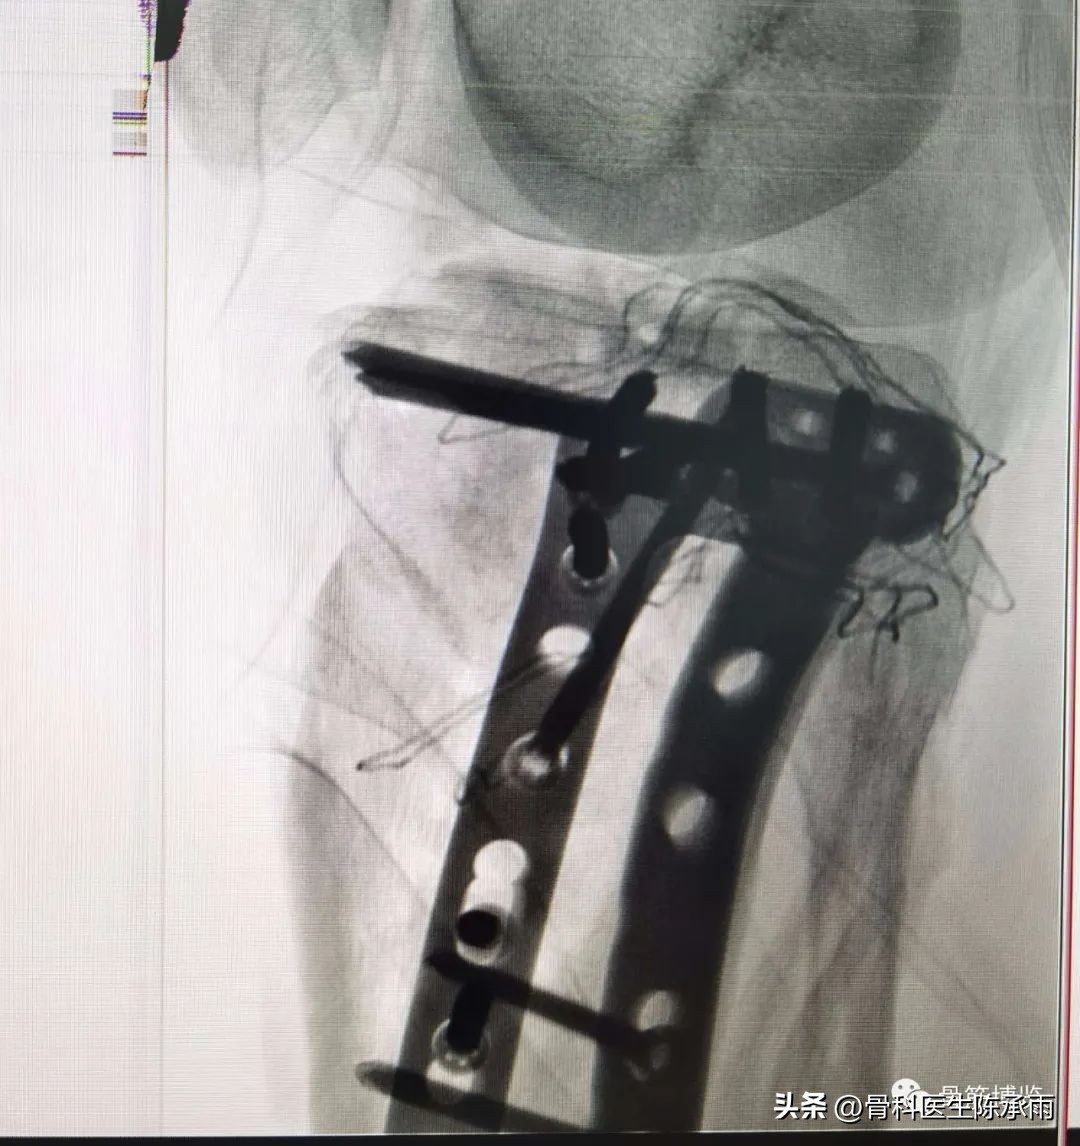

1例

2例

3例

4例

5例

6例

7例